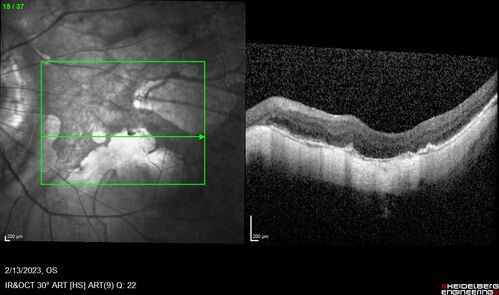

Myopic CNVM Left Eye

80 year old female. VA dropped to 20/125 but improved back up to 20/50 with Vabysmo